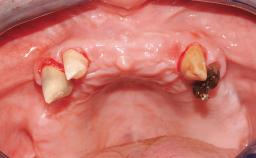

A 31-year-old man presented to our clinic 30 days after a motor vehicle accident in which he had suffered a dentoalveolar fracture in the anterior maxilla, including avulsion of teeth 12 and 11 and luxation of tooth 21. He was first treated on the night of the accident in a small city hospital with no oral and maxillofacial surgeon on the staff. A wired retention had been applied and the teeth repositioned to the best of the clinicians’ abilities. When he first presented to our care, the patient showed extrusion of teeth 12 and 11 associated with gingival recession due to bone loss in the anterior maxilla, and the stainless steel wires were still present.

Soft Tissue Anatomy Intact Defective

Bone Volume Horizontally and vertically sufficient Horizontally deficient Deficient vertically or deficient vertically AND horizontally

Soft Tissue Contour and Volume Significantly deficient